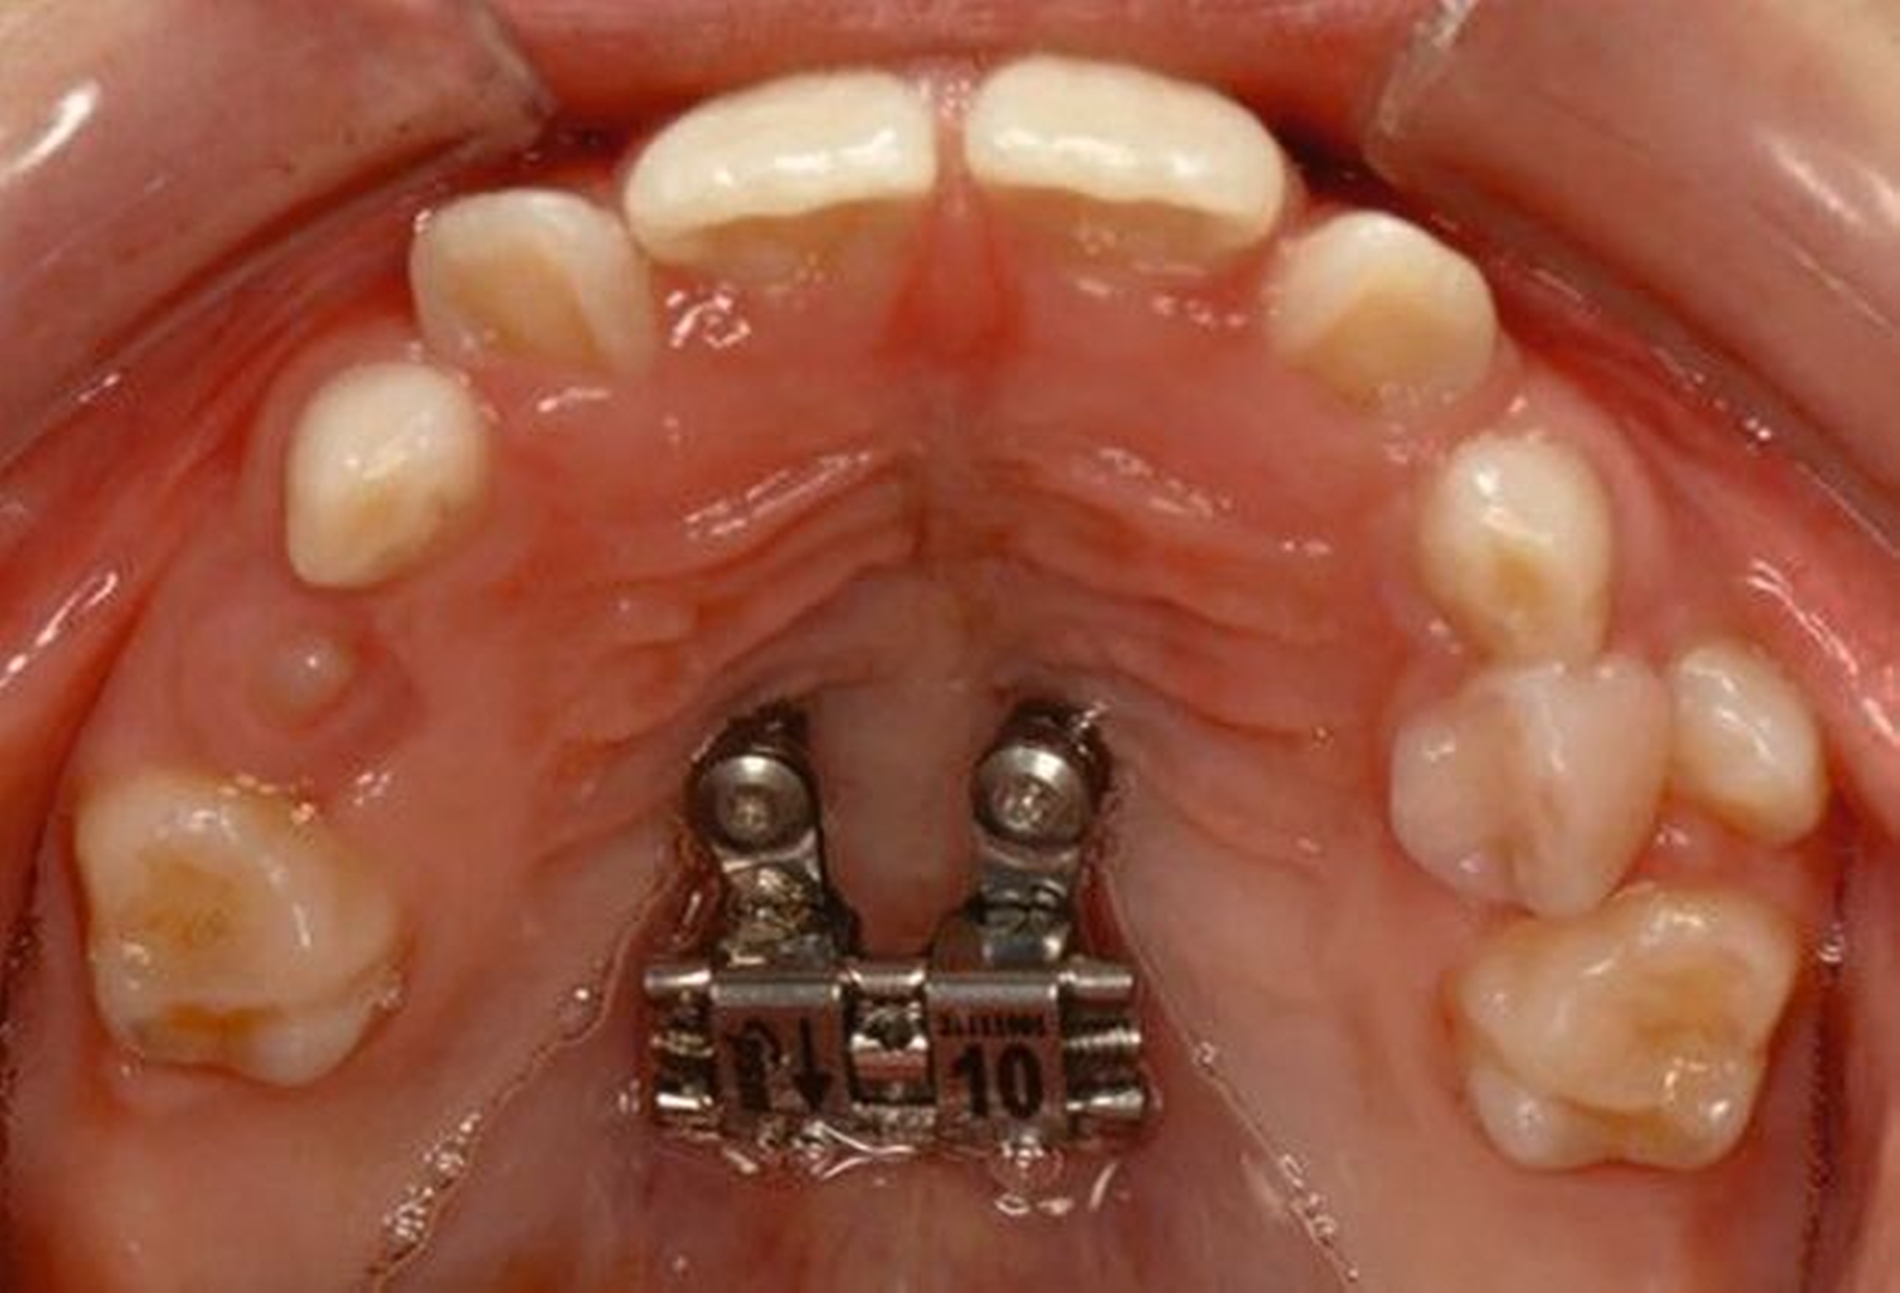

Die Zähne 36, 37, 46 und 47 wurden in Allgemeinanästhesie chirurgisch freigelegt. Zusätzlich wurden die beiden paramedianen Mini-Implantate (2 x 9 mm, Benefit System; PSM North America, Indio, CA) ohne Vorbohren mithilfe der zuvor hergestellten Schablone inseriert (Abbildung 3). Für die Platzierung der Mini-Implantate wurde ein Winkelschraubendreher verwendet. Direkt nach der Operation wurde die bmx DIRECT Hyrax-Schraube (10 mm, BENEfit®-System, Dentalline, Birkenfeld, Deutschland) an den Mini-Implantaten befestigt, um ein MARPE zu erzielen (Abbildung 4).

Die Eltern des Patienten wurden angewiesen, die Schraube einmal täglich zu aktivieren. Die gesamte Aktivierungszeit der Hyrax-Schraube betrug circa zehn Wochen. Während dieser Zeit vergrößerte sich die transversale Dimension des Oberkiefers um sieben Millimeter im posterioren Bereich (Milchmolaren) und um fünf Millimeter im anterioren Bereich (Milcheckzähne). Währenddessen trat ein mediales Diastema auf (Abbildungen 4b und 4c), das auf eine skelettale transversale Expansion des Oberkieferknochens hinwies. Nach der aktiven Expansionsphase der Hyrax-Apparatur wurde das Gerät für weitere Behandlungszwecke verwendet: Erstens als Retentionsgerät, um die bereits erzielte transversale Oberkieferbreite zu halten und zweitens als skelettal verankerte Apparatur zum Einstellen der retinierten und verlagerten Zähne mithilfe individuell angefertigter Kragarme. Hierfür wurde die Hyrax-Apparatur im zahntechnischen Labor modifiziert, indem Kreuzröhrchen für eine stationäre Befestigungen für die Drähte des Kragarms angebracht wurden.